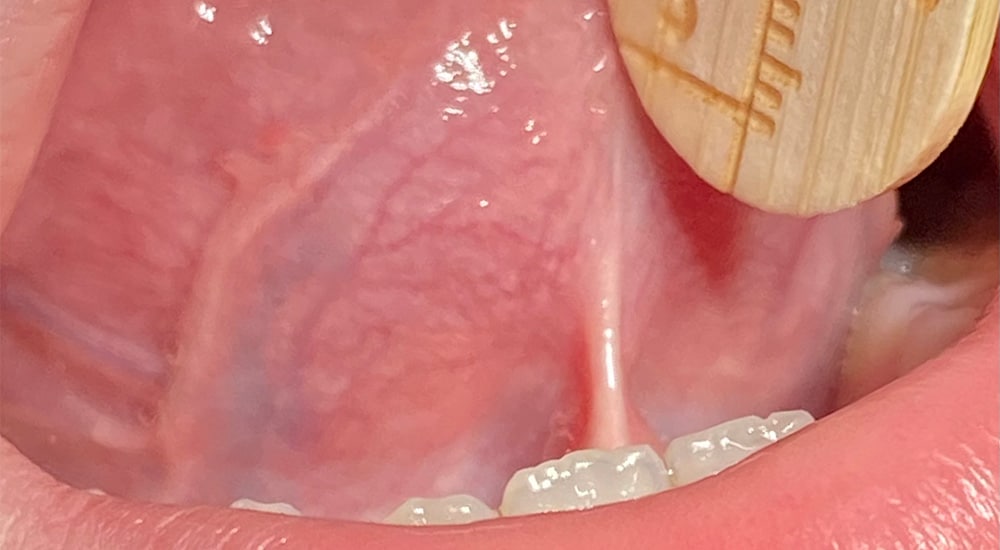

Evaluation anatomique frein langue

Présentation d'un cas clinique de frénectomie linguale....